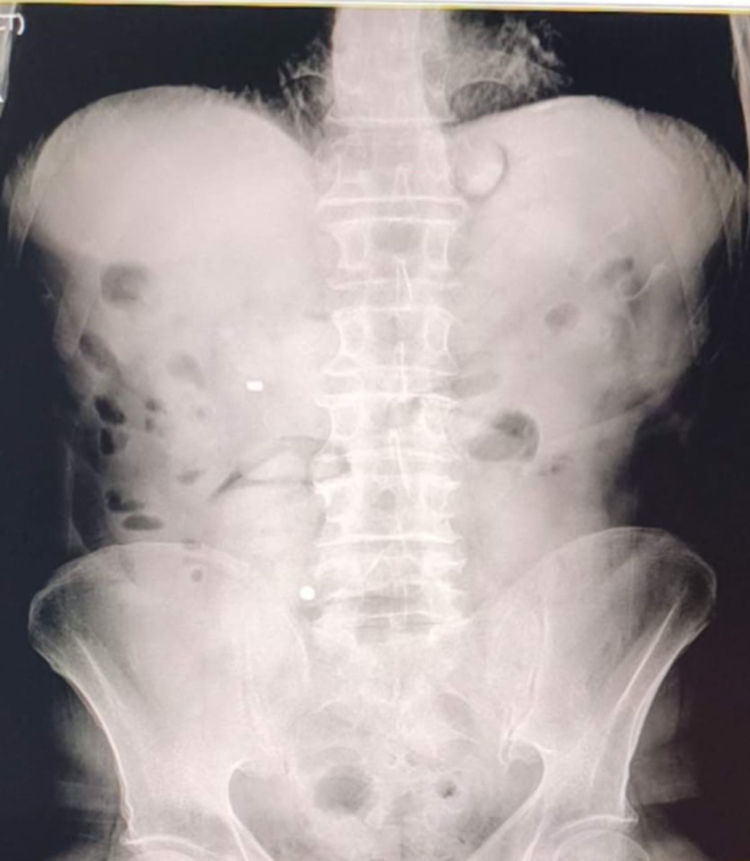

Uşak İl Emniyet Müdürlüğü Narkotik Suçlarla Mücadele Şube Müdürlüğü ekipleri, "Uyuşturucu Madde Ticareti" ile mücadele çalışmaları kapsamında yürütülen çalışmalar ve takipler neticesinde il merkezinde bir taksiyi durdurdu. Takside yolcu konumunda bulunan İran uyruklu D.G. ve A.C. gözaltına alındı.Şüphelilerin hastanede yaptırılan kontrolleri ve çekilen röntgen filmleri sonucunda mide ve bağırsaklarında çok sayıda uyuşturucu madde içeren kapsül bulunduğu tespit edildi. Hastanede kontrollü şekilde gözetim altında tutulan şüphelilerden tıbbi müdahaleler neticesinde toplam 93 parça halinde 1 kilo 70 gram metamfetamin ele geçirildi.